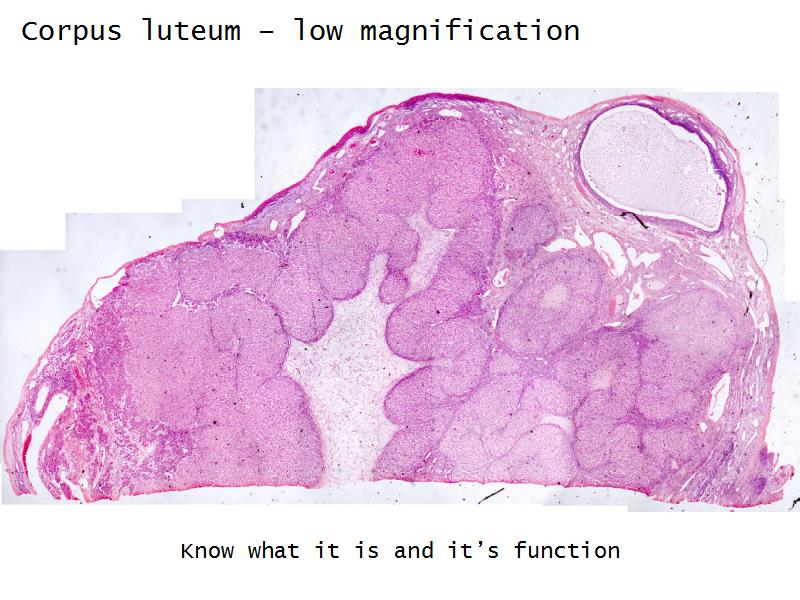

- Corpus luteum

- Slide 91: Corpus luteum